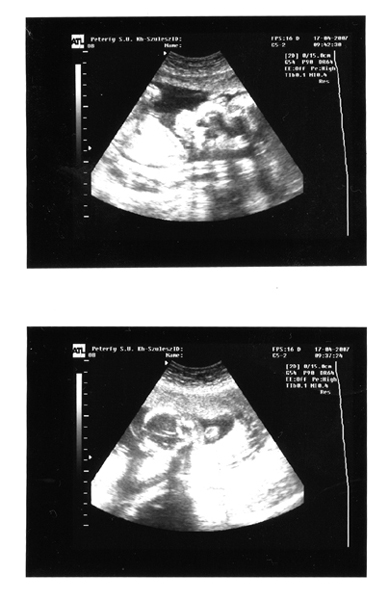

Tegnap pedig voltunk 2D és 4D-n. Sajnos nem akart felénk fordulni, és az arcát is mindig takarta az egyik kezével, de amikor a szívhangot meghallgattuk, hát majdnem elpityeredtem. Apa is a könnyeivel küzdött...

Fantasztikus érzés volt! Szerintem most tudatosult igazán bennünk, hogy egy külön kis emberke fejlődik odabenn, akinek máris személyisége van!